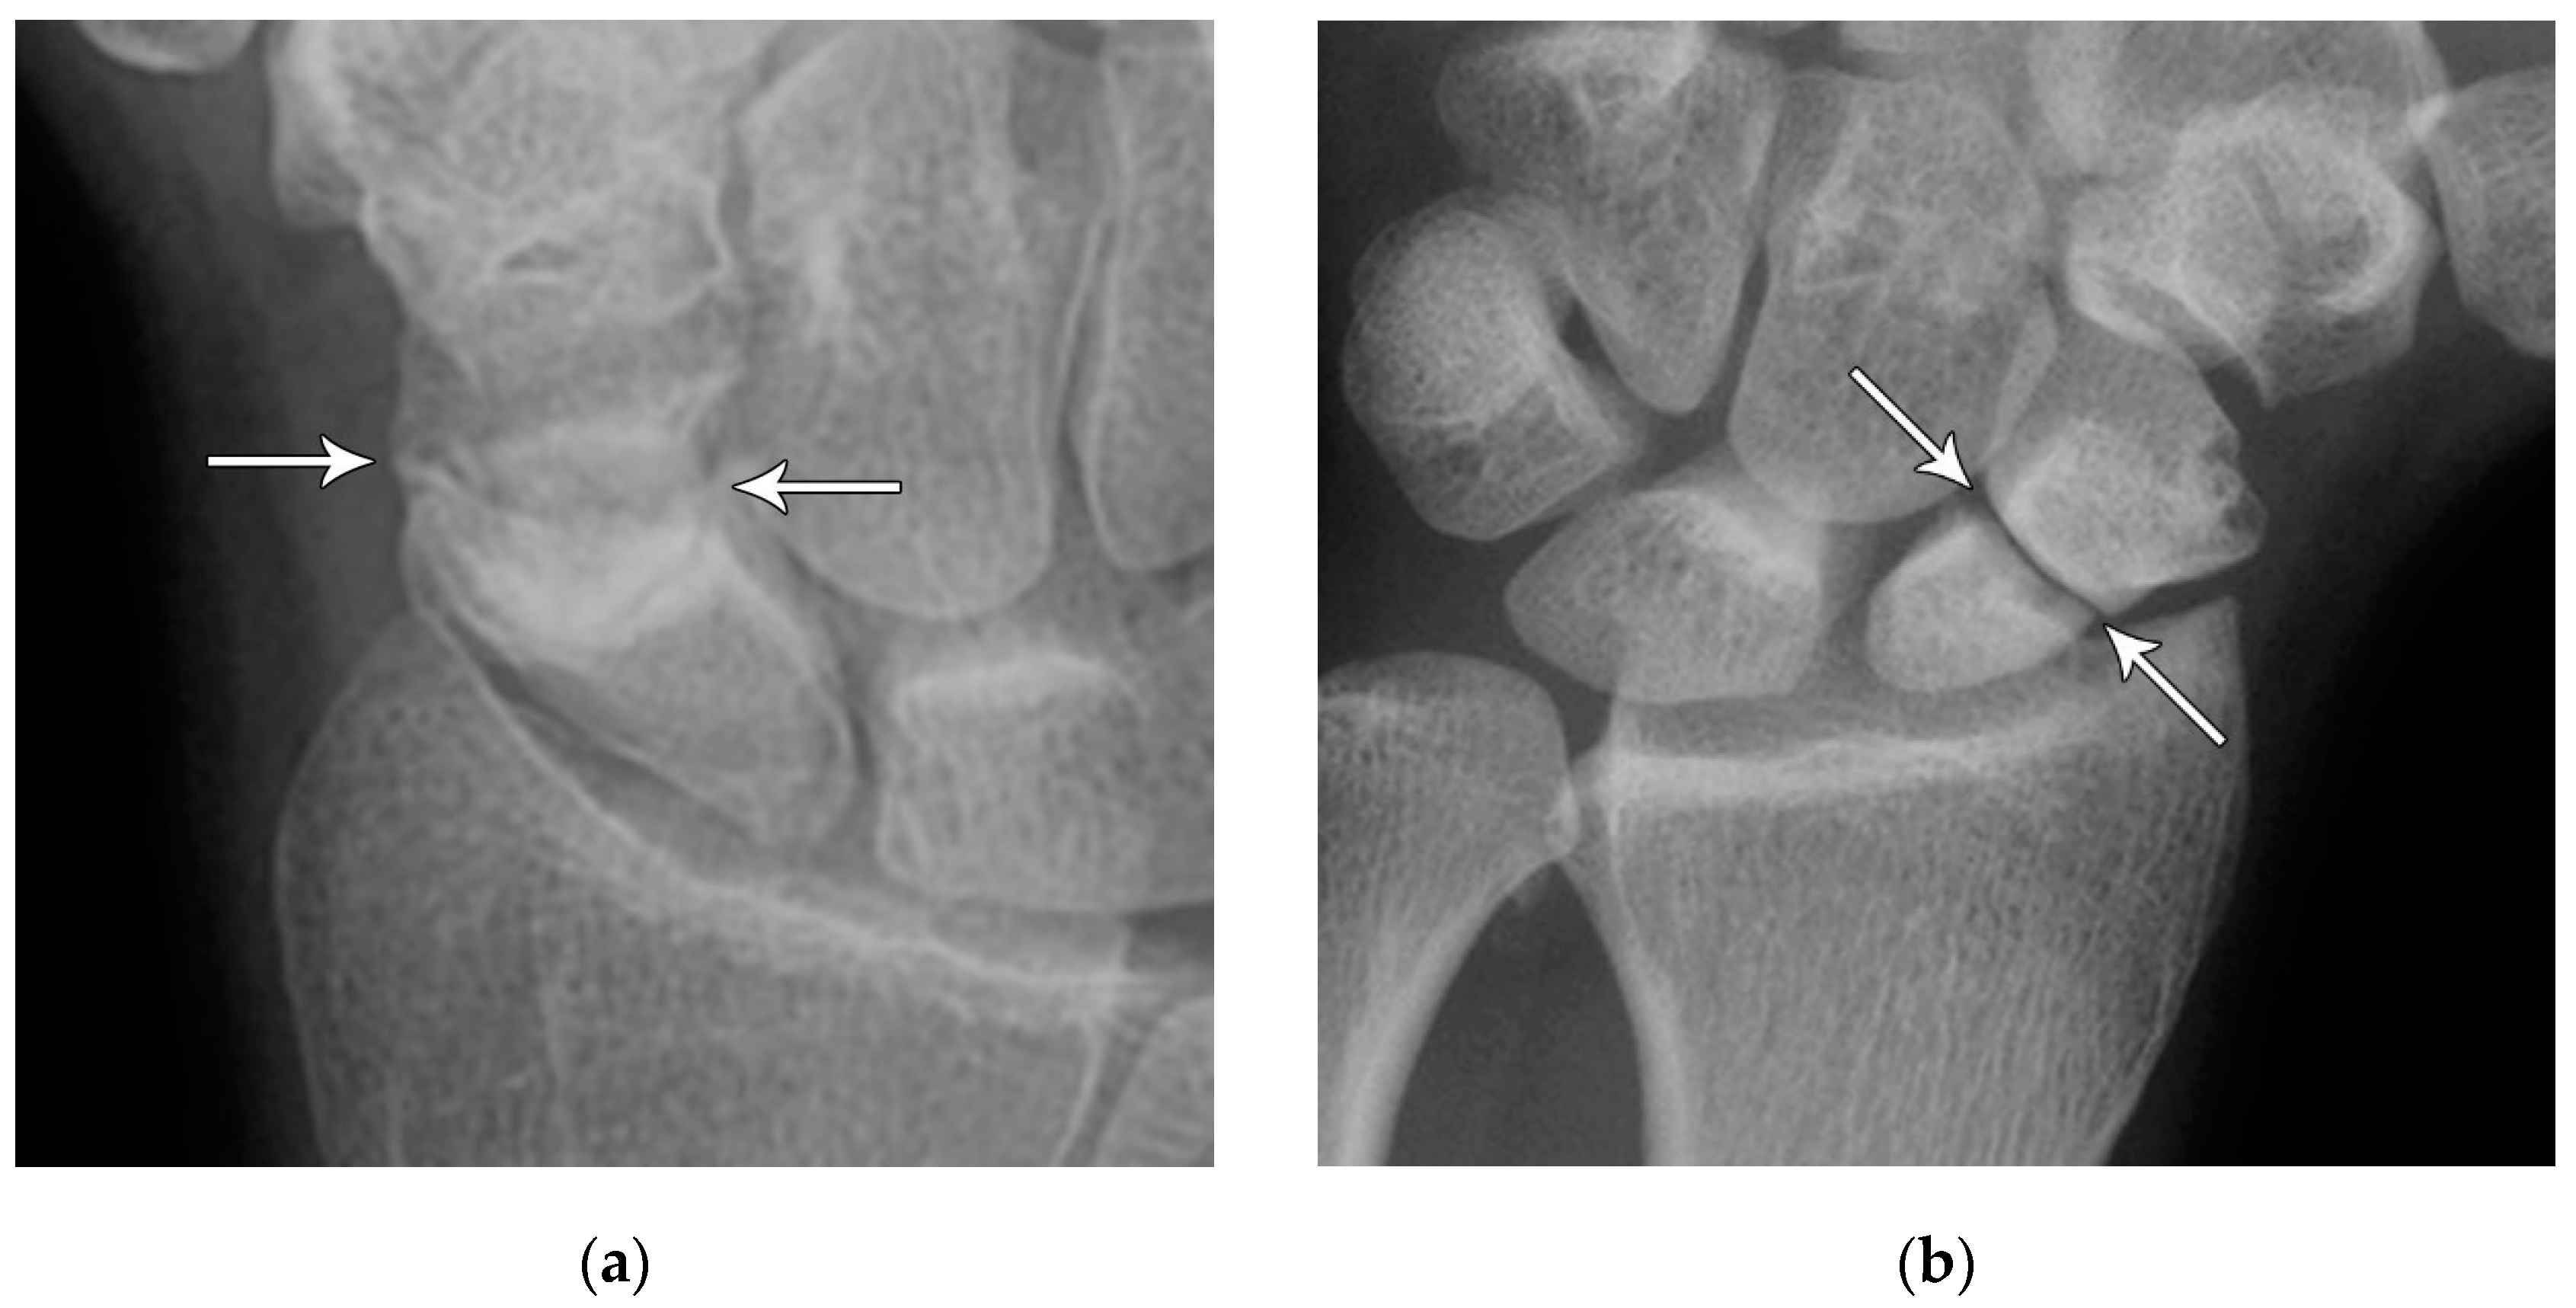

Figure 10. (a) PA radiograph of the wrist showing a triquetral body fracture (arrow) and concurrent scaphoid fracture (arrowhead). (b) Coronal reformatted CT confirms these findings with greater detail. (c) Lateral radiograph of the wrist showing a dorsal cortex fracture of the triquetrum with a tiny, avulsed fragment (curved arrow).

The next most common carpal fracture is the triquetral fracture. Most of these occur on the dorsal aspect of the triquetrum and are best identified on the lateral radiograph at the dorsal aspect of the triquetrum and are best identified as the so-called “pooping duck sign”. These result from compression of the ulnar styloid process and the dorsal aspect of the triquetrum during forceful ulnar deviation and wrist hyperextension [4,5]. Triquetral fractures are subdivided into body, volar cortex, and dorsal cortex fractures, with the latter being the overwhelming majority. Triquetral body fractures (Figure 10A,B) are injuries that are often associated with intrinsic ligamentous injury such as a lunotriquetral tear. Dorsal cortex fractures (Figure 10C) represent avulsions of the combined attachment of the dorsal radiocarpal and dorsal intercarpal ligaments. Management of dorsal cortex fractures and nondisplaced body fractures consists of 3 to 6 weeks of cast immobilization. If there is concomitant intrinsic ligamentous injury such as a lunotriquetral ligament tear, this injury is unstable and requires surgical stabilization [17].